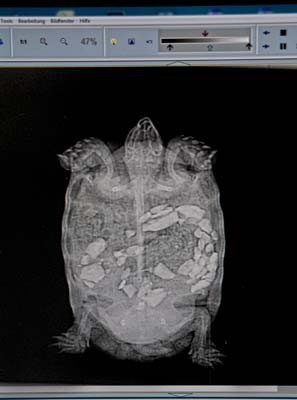

Digitales Röntgen

Seit 2008 fertigen wir in unserer Ordination digitale Röntgenbilder an. Durch die computergestützte Bildbearbeitung können Helligkeit und Kontrast auf dem Bildschirm verändert und Details beliebig vergrößert oder vermessen werden. Das ermöglicht uns als Tierärzten eine viel sicherere Beurteilung des Röntgens und dient gleichzeitig dem Umweltschutz, weil wir keine giftigen Chemikalien zur Bildentwicklung benötigen. Im Dezember 2019 haben wir ein Upgrade vorgenommen und verfügen jetzt über die neueste Technologie!